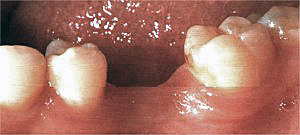

Fehlender 1. Molar im Unterkiefer, links.

Fall Nr. 2

Die einzementierte Krone fügt sich in Farbe und Form harmonisch in die bestehende Zahnreihe ein.